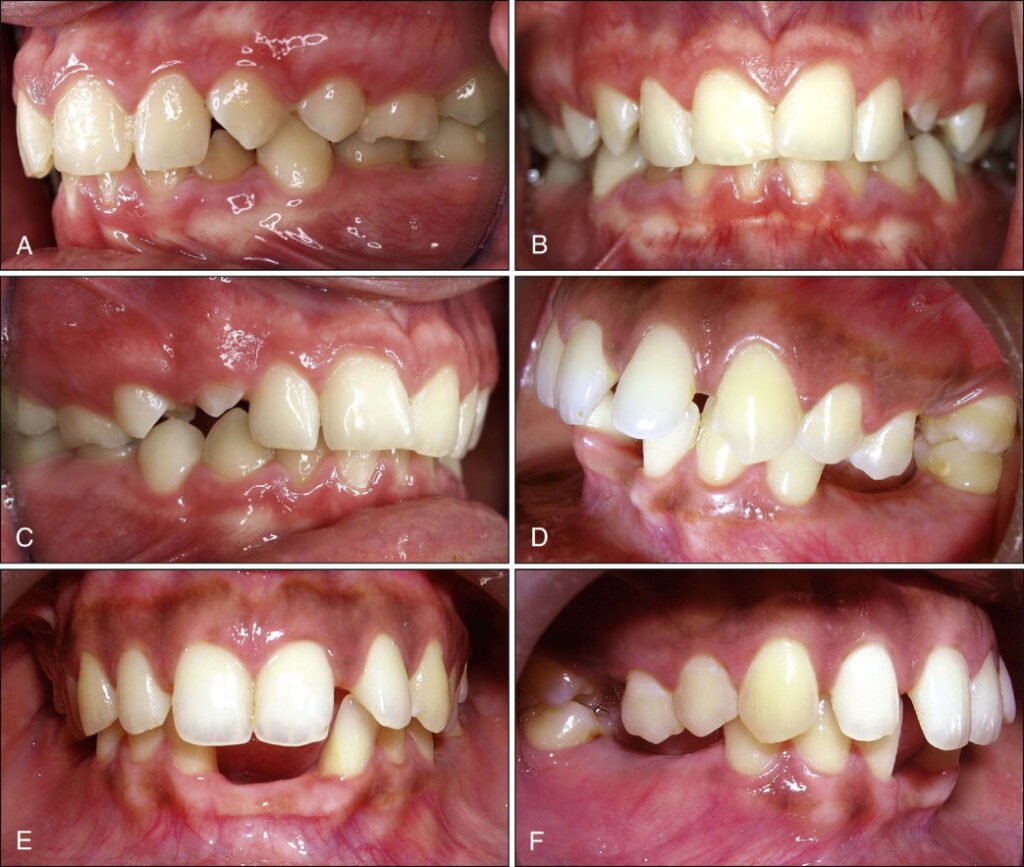

Cas Clinique 1 : Supraclusion en Denture Mixte — Interception Précoce

Patient : Mélanie, 8 ans. Consulte pour contrôle orthodontique. Antécédents familiaux de supraclusion côté maternel.

Présentation : Recouvrement incisif de 6 mm, courbe de Spee prononcée à l’arcade inférieure. Direction de croissance antérieure (angle goniaque fermé). Les incisives temporaires supérieures viennent de tomber. Ventilation nasale correcte, pas de dysfonction linguale.

Problématique : Supraclusion alvéolaire en cours d’installation, terrain héréditaire défavorable, moment clé (post-chute des temporaires) pour l’interception.

Prise en charge : Pose immédiate d’une plaque inter-incisive palatine avec prolongement antérieur recouvrant le site d’éruption. La plaque est portée 22 h/24. Contrôle tous les 3 mois. Après éruption partielle des incisives permanentes (3-4 mm), transition vers un bionator de Balters modifié avec équiplan de Planas pour maintenir le guidage et prévenir l’approfondissement.

Résultat attendu : Réduction progressive du recouvrement incisif, guidage de l’éruption dans un angle d’attaque correct. Contention indispensable en fin de phase active, avec suivi jusqu’en denture permanente complète.

Point pédagogique : L’interception précoce en denture mixte, au moment précis de la chute des temporaires, est la fenêtre thérapeutique idéale pour la supraclusion. La retarder d’un an peut faire manquer l’opportunité de guider l’éruption.